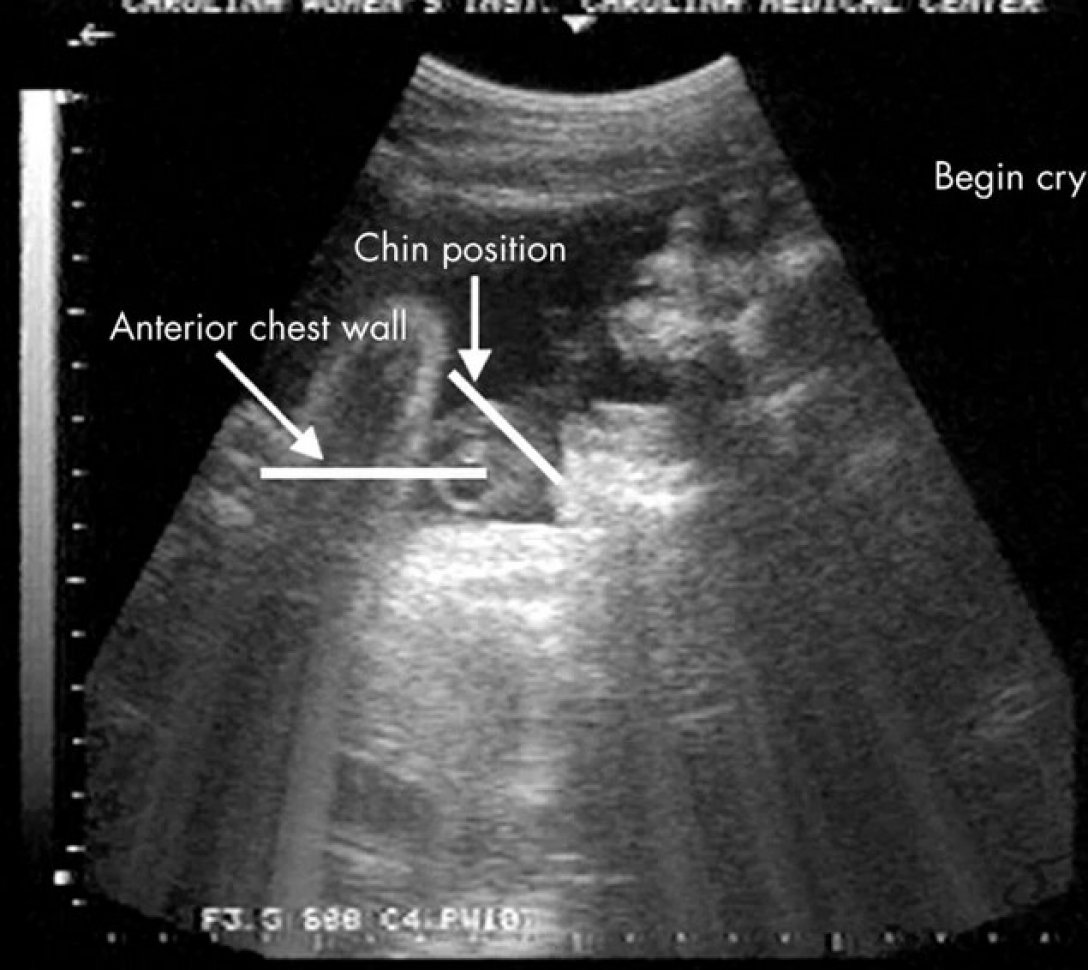

Во время стимуляции младенец широко открыл рот, сделал несколько выдохов и запрокинул голову, все закончилось дрожью подбородка. Подобное поведение было замечено у 10 младенцев. Был ли это плач? Все зависит от того, что вы подразумеваете под плачем, говорят ученые.

Рейссланд и ее коллеги изучили выражения лица плода в утробе с помощью 4D ультразвуковой визуализации. Они определи две формы мимики, которые они назвали "плачущее лицо" и "смеющееся лицо". По их словам, эти выражения лица является предшественниками того, как будет действовать ребенок после рождения.

Эти выражения лица развиваются в период примерно от 24 до 35 недель, и эта мимика становится сложнее с продолжением развития плода. Таким образом ребенок готовится к тому, чтобы издать свой первый крик после рождения, говорят ученые.

Подобная мимика у ребенка появлялась без какой-либо внешней стимуляции со стороны ученых. И они не знают делает ли плод попытки издать звук, хотя даже если бы младенец и пытался это сделать, звуковая волна будет слишком слабой, чтобы ее можно было услышать. Также неизвестно связано ли плачущее выражение лица с дискомфортом у плода.